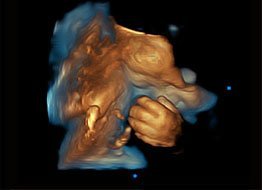

Imágenes Cardiológicas